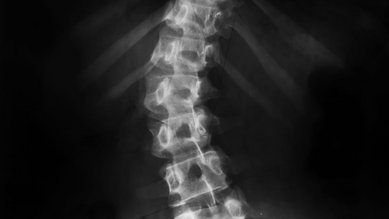

الجنف في سن المراهقة

في حالة الجنف في سن المراهقة، يصبح العمود الفقري معوجًا. وسبب ذلك غير واضح. إذا استمر الانحناء، فيجب فحصه بانتظام.